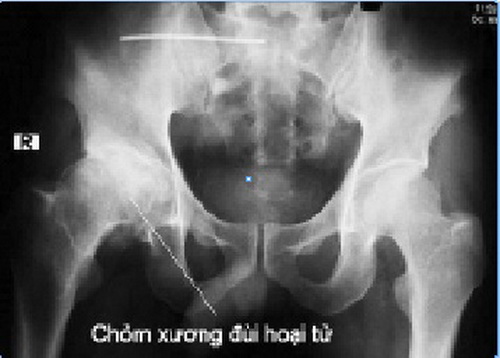

Chụp X Quang

Kĩ thuật chụp hình bằng tia X, hay còn gọi là chụp X Quang, thường là phương pháp chẩn đoán đầu tiên mà các bác sĩ sẽ chỉ định tiến hành. Một cách đơn giản để tạo ra những hình ảnh thực tế của xương, chụp X Quang thường rất hữu ích trong việc chẩn đoán nguyên nhân gây đau khớp. Tuy nhiên, đối với bệnh hoại tử xương, tia X lại không đủ nhạy để có khả năng phát hiện ra những biến đổi của xương trong giai đoạn đầu phát bệnh. Vì vậy, trong trường hợp kết quả chụp X Quang là bình thường, bác sĩ có thể yêu cầu cho bệnh nhân tiến hành thêm một số kĩ thuật chẩn đoán khác nhằm tăng tính chính xác cho kết quả cuối cùng. Trong những giai đoạn sau của tình trạng hoại tử xương, ảnh chụp X Quang có thể cho thấy các thương tổn ở xương, và sau khi chẩn đoán đã được đưa ra, phương pháp này thường sẽ được sử dụng nhằm theo dõi tiến triển của bệnh.